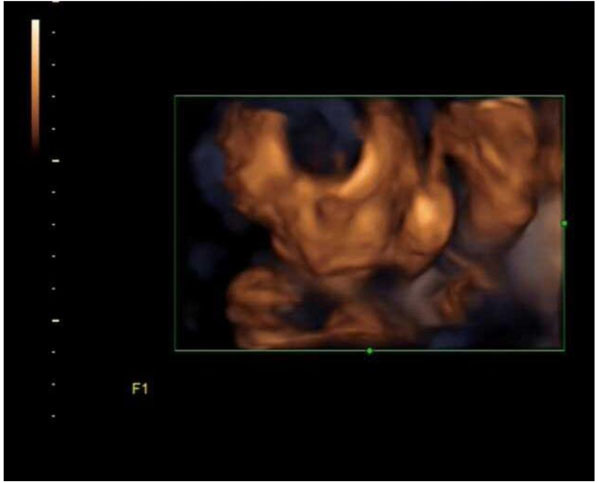

Fig. (2I). 4D Ultrasound Imaging of Fetal Face at the beginning of the test for a Group A Patient. Facial feature is unclear because its blocked by the hand and arms of the fetus.

Fig. (2II). Successful 4D Ultrasound Imaging of Fetal Face with clear features Post 5 minutes of Knee-Chest Decubitus Positions in the same Group A patient as in Picture 1. [I].